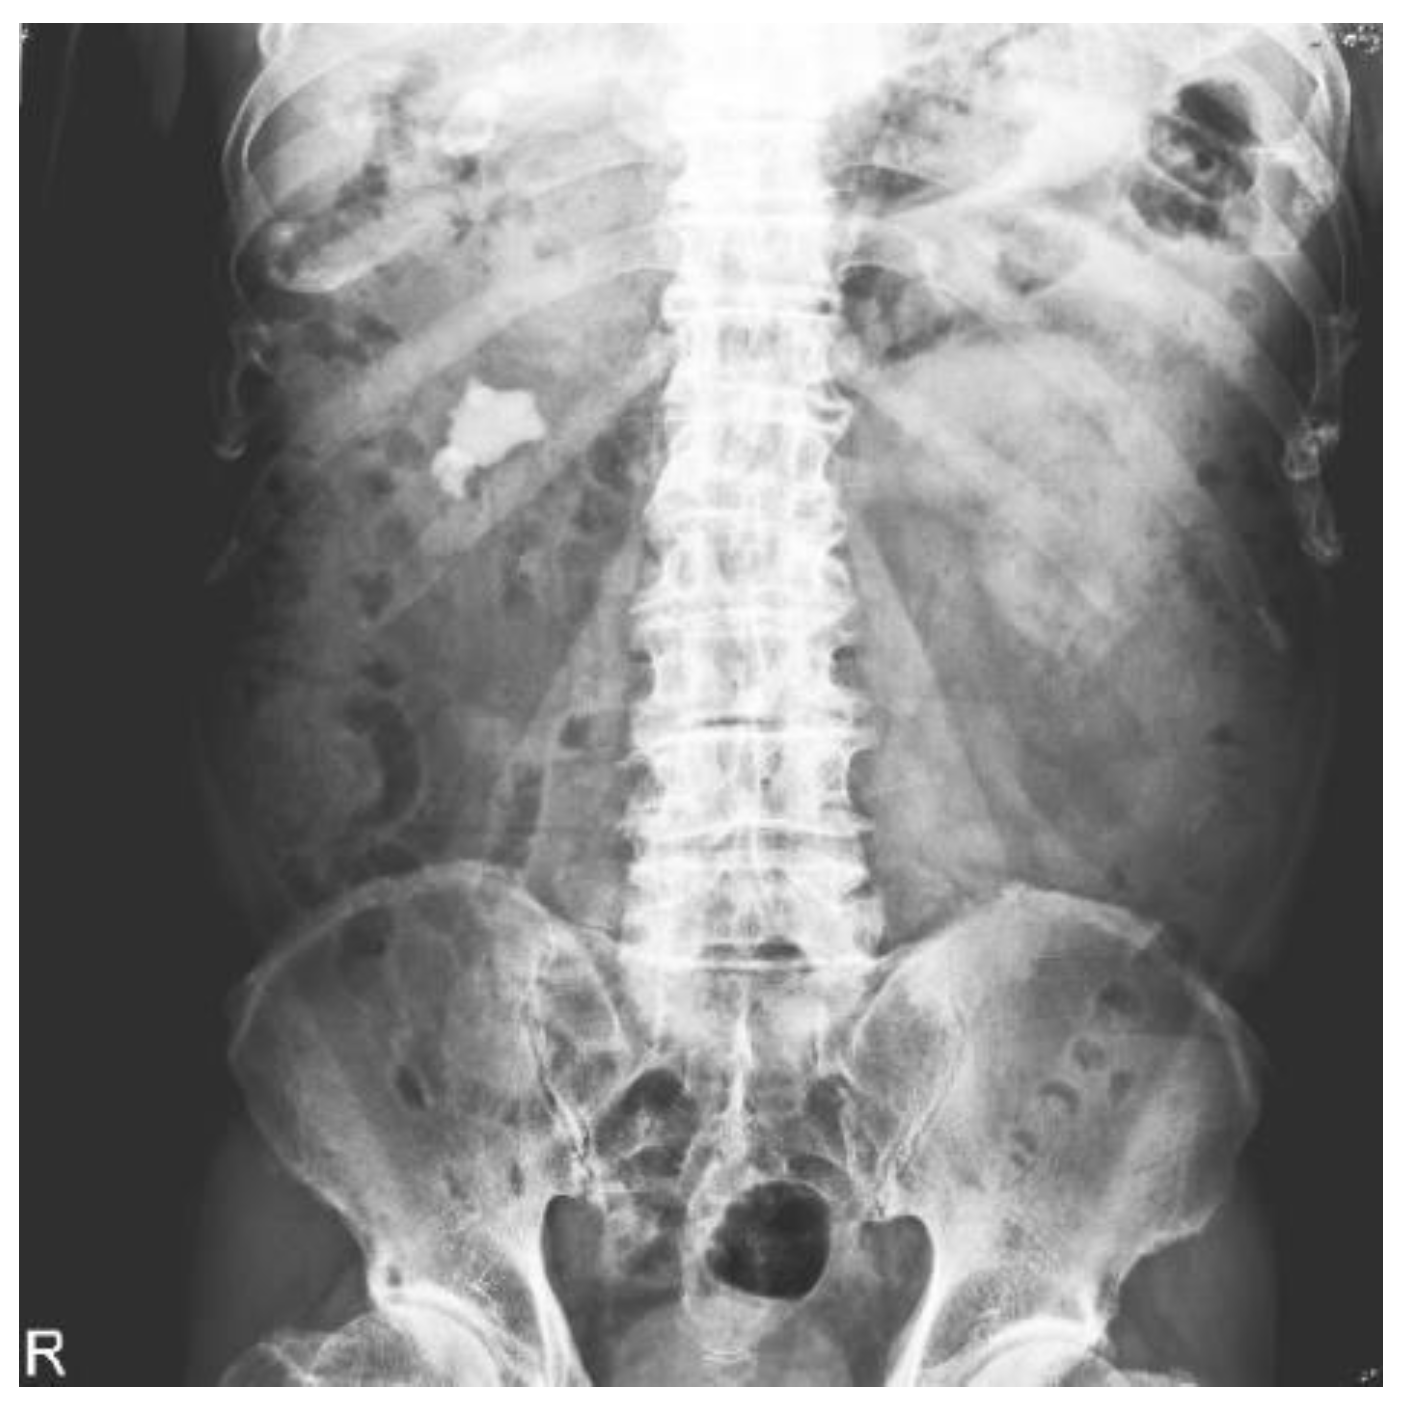

2.2. Datasets

2.3. Image Preprocessing